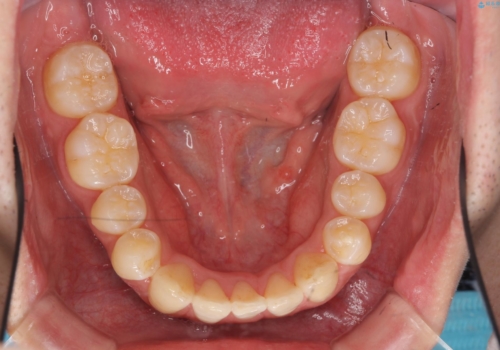

- 前歯のガタガタを主訴に来院。

下の前歯は一本保険治療での被せ物になっており、変色していました。

・神経のない下の前歯を残す

・神経のない歯を抜いてしまって、天然歯で閉じる

のプランを提案し、神経のない前歯を抜く選択をされました。

下の前歯が3本になり奇数になることで、上下の真ん中は一致しませんが、そこまで目立たないと思います。

残りは全て天然歯になり、人工物の心配をしなくて済むようになりました。

ブラックトライアングルも少なめで、短期間でしっかり並びました。

下の前歯の歯槽骨が一番薄く、歯肉退縮のリスクがあるため、今回のような1本抜歯も選択肢の一つです。